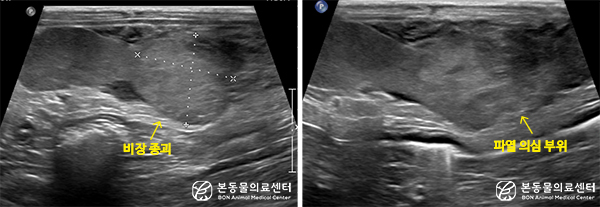

초음파 검사 상 비장 실질 내 약 2.2 x 2.4cm 크기의 종괴 음영 확인되며, 일부 변연은 연결성이 소실된 상태

연결성이 소실된 종괴 주변으로 광범위한 혈괴 의심 소견 및 중등도 복수 저류

복부 방사선 검사 상 비장 일부가 종대되며, 복수 저류가 의심되는 소견을 보였고, 복부 초음파 검사 상 비장 실질 내 약 2.2 x 2.4 cm 크기의 종괴 음영 확인되며, 일부 변연은 연결성이 소실되며 이 주변으로 다량의 복수 및 혈괴 의심 소견을 보였습니다.

추가적으로 복수 천자 시 혈복으로 확인되어 비장 종괴 파열에 의한 혈복으로 진단하였습니다.